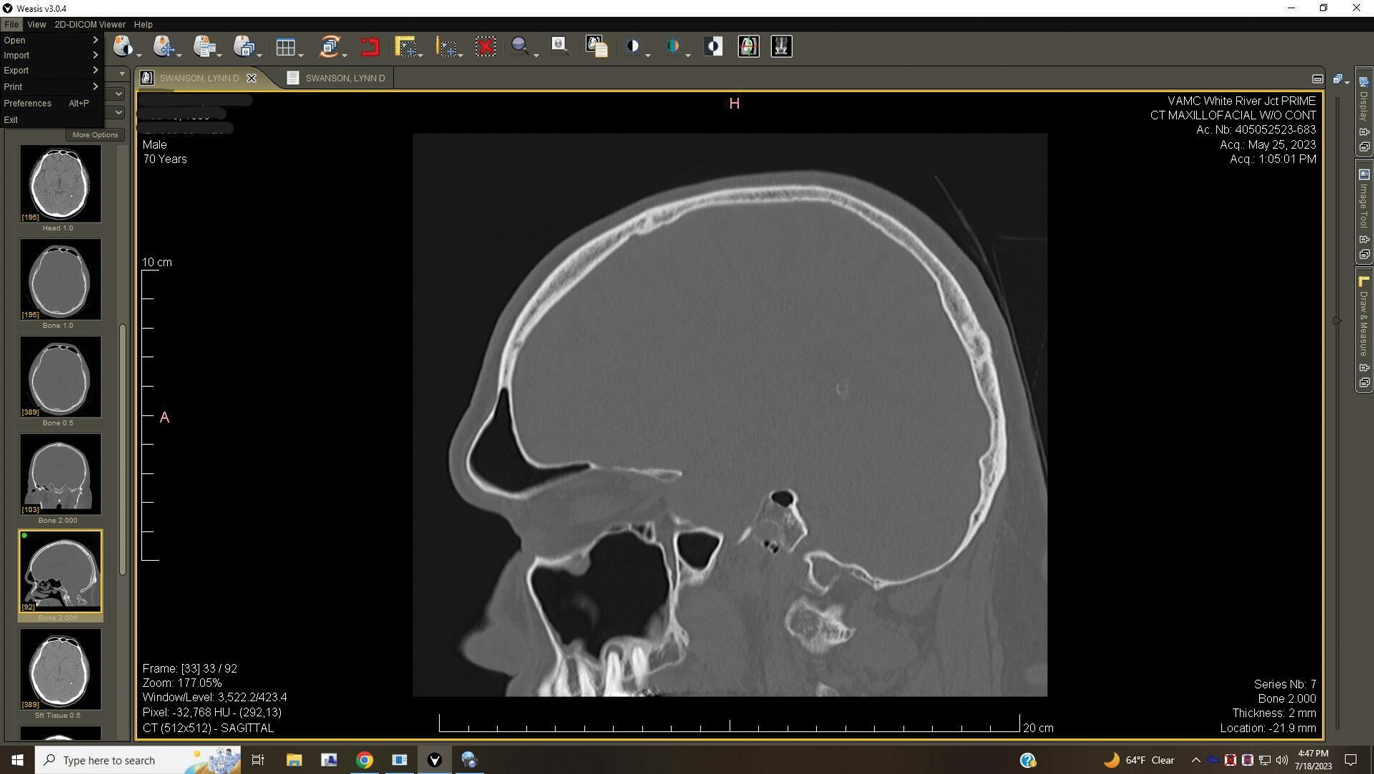

A 52-year-old male patient was seen by his otolaryngologist for symptomatic and unilateral sinusitis of 6 months duration. Medical CT showed dental pathology (Figure 5). His general dentist had a bitewing radiograph on file and referred the patient for endodontic evaluation (Figure 6).

Fig 5. Case 2. Preoperative CT imaging from otolaryngologist showing periapical radiolucency associated with tooth No. 14 and associated maxillary sinus mucositis.

Figure 5